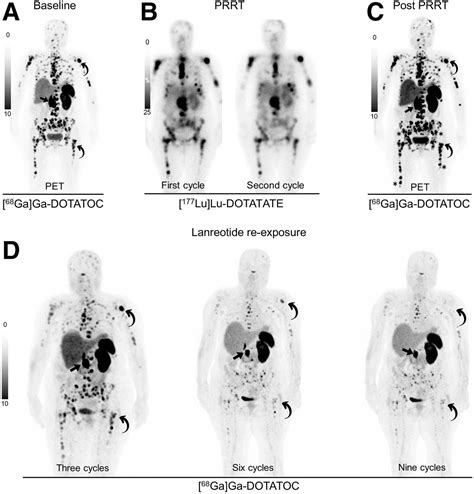

• Treatment Planning: By identifying precisely where the tumors are, surgeons or oncologists can better decide on the most effective course of treatment, such as surgery, radiation, or specialized medical therapies like peptide receptor radionuclide therapy (PRRT).

• Monitoring Progress: It can be used to assess how well a current treatment is working or to check for recurrence after treatment has been completed.